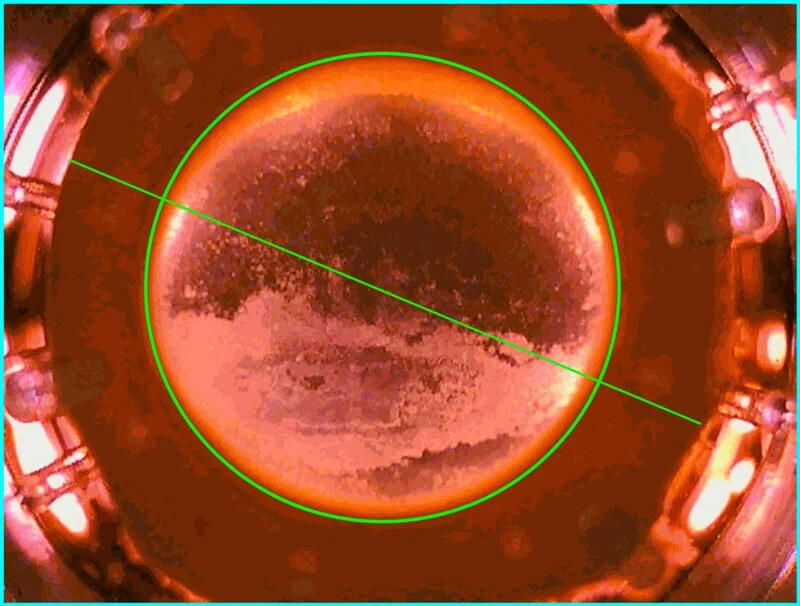

CellChek® D+ features a patent applied for “Donor Enhance” imaging system that provides remarkable views of endothelium, intra-stromal structure, and the epithelium. The range of new information from which to make better clinical decision is valuable: blood cells, fungus, rough keratome cuts, dead cells, epithelial anomalies. Never have we had this view of pre-implanted material. Corneal surgeons are finding this information to be illuminating in helping to understand graft success and failure.

Full Graft Imaging

CellChek® D and D+ provide a total picture of the cornea. Use digital measurement tools to identify, measure and document cornea dimensions, defects, and scars.